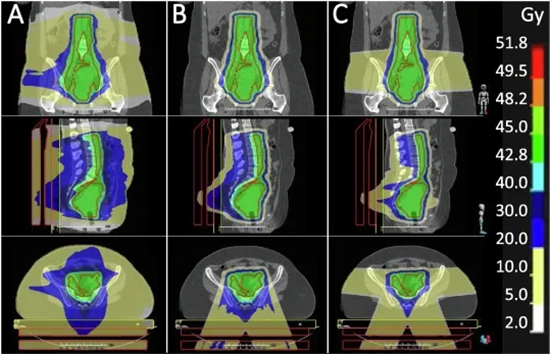

2015年,德国一项大型研究表明,与光子放疗相比,质子治疗在宫颈癌治疗中能够更好地保护小肠和直肠,显著降低急性和晚期毒性。荷兰的研究也进一步验证,质子治疗相比光子放疗能够更好地保护宫颈癌治疗中的危及器官,如骨髓、骨骼等,降低副作用的发生。

A为光子,BC为质子